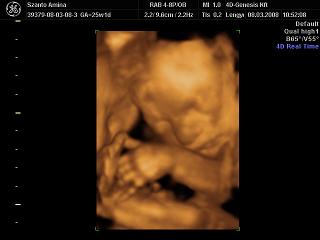

Bence 18 hetesen

És egy tappancs 2008.03.08 19:45